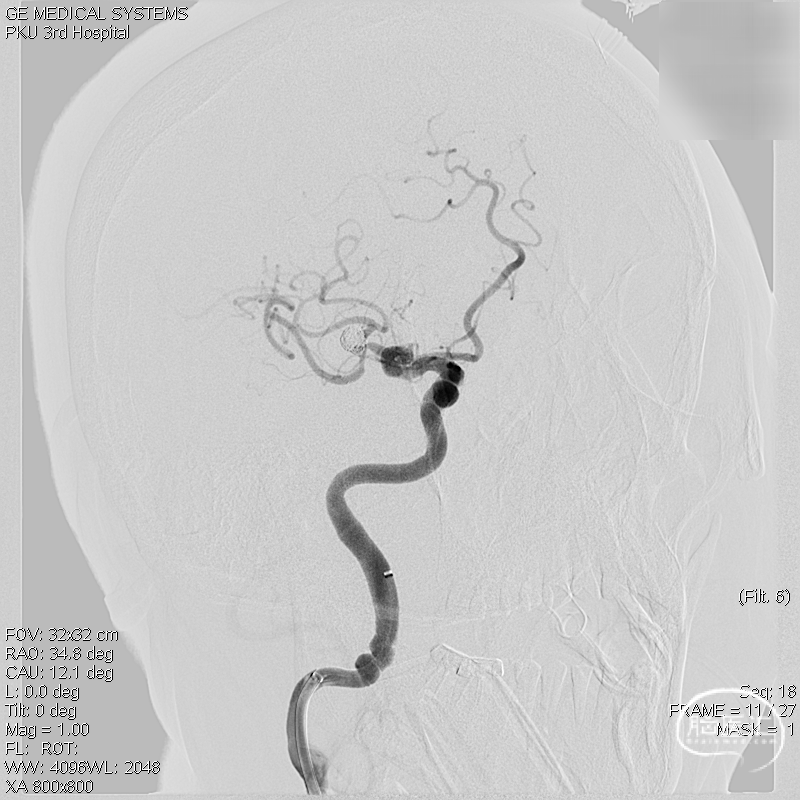

术前影像:术前正侧位。

术前影像:术前工作位。

三维重建:显示左侧MCA分叉部未破裂动脉瘤,约8.2mm*8.6mmm,瘤颈3.8mm,顶端有子瘤。

术前工作位与三维重建:显示右侧MCA分叉部未破裂动脉瘤,6.9mm*7.2mm,瘤颈7.4mm。该病例之困难在于M1迂曲成袢。